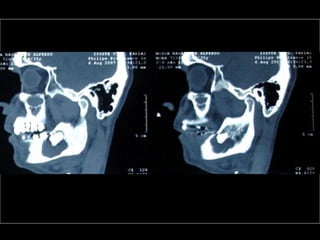

Tomografía computarizada

De seno maxilar corte sagital.

Area de implantación

Dentaria.

Material osteoconductor

para elevar el piso antral

Nuevo piso del seno y su

margen de seguridad para

contener el implante

dentario

Tomografía computarizada De senomaxilar corte sagital. Area de implantación Dentaria.

Nuevo piso delseno y su margen de seguridad para contener el implante dentario